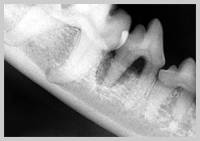

Radiograph showing more than 50% attachment loss of mesial root

Attachment loss is now greater than 50%. If disease is generalised, horizontal bone loss is most likely, whereas localised lesions, such as the palatal aspect of the maxillary canines, may present infrabony pockets with vertical bone loss.